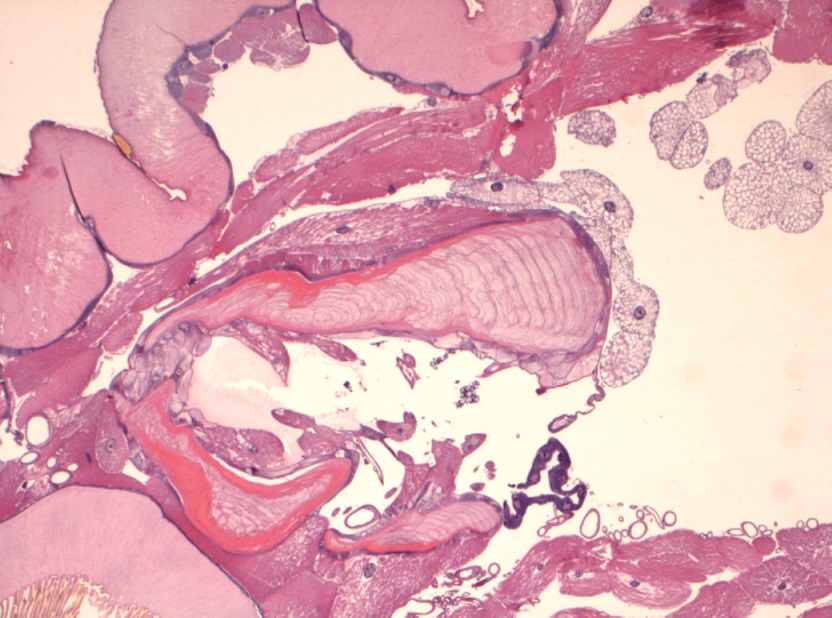

Foto microscopiche: purtroppo non ho potuto fare foto "panoramica"; ho fatto alcune foto al minore ingrandimento; si possono osservare le componenti della larva caratterizzata da spessa cuticola con sparse "spine" in superficie, che penso che siano i rostri; internamente alla cuticola si osserva strato di tessuto muscolare liscio ed organi interni conservati; ho fatto anche una foto del lembo di cute e sottocute sovrastante centrato da tragitto fistoloso circondato da denso infiltrato infiammatorio costituito da linfociti, plasmacellule, istiociti e più rari granulociti eosinofili.

Io vi metto due foto macroscopiche e quelle istologiche, che in pratica rappresentano le "fette" della larva partendo da un'estremità (bocca?), poi il centro (forse l'apparato digerente?) e l'altra estremità...spero siano sufficienti :)

It is the larvae of subcutaneous warble fly (Hypodermatinae).

The characteristic feature from larvae sclerosed presence of strong hooks arranged in a ring.